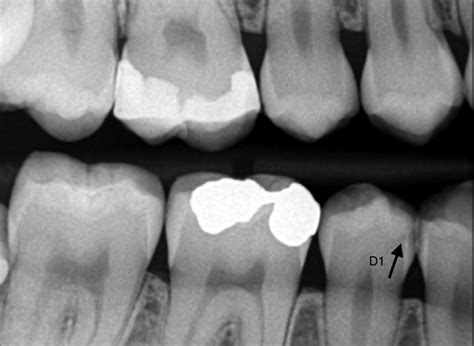

Además de la identificación de lesiones oclusales y de las superficies lisas, la detección clínica de lesiones cariosas proximales desempeña un papel destacado, si bien esta medida resulta difícil de adoptar debido a la visibilidad casi siempre insuficiente. Las radiografías interproximales posibilitan el diagnóstico de lesiones proximales clínicamente invisibles o poco visibles y proporcionan información tanto sobre su extensión como sobre su ubicación.

Cualquier tipo de radiografía no es útil para diagnosticar las caries. Las idóneas para la detección de caries son las radiografías periapicales o las de “aleta de mordida”. Son radiografías de pequeño tamaño y alta sensibilidad que nos muestran con gran detalle las coronas y raíces de los dientes.

La desmineralización y destrucción de las capas del diente se observa como una imagen radiolúcida (zona negra alrededor/dentro del diente). En la consulta dental realizamos controles radiográficos periódicos. Se hacen cada 6, 9 o 12 meses, dependiendo del riesgo de caries del paciente, la presencia de múltiples reconstrucciones interproximales (interdentales), etc.

Es importante tener en cuenta que el diagnóstico temprano de las caries repercutirá en un mejor pronóstico del diente. En obturaciones antiguas (empastes/reconstrucciones) controlaremos que los márgenes de las restauraciones estén correctos, ya que en el material artificial no se producirán caries, pero en el tejido dental de alrededor sí podrían aparecer filtraciones.